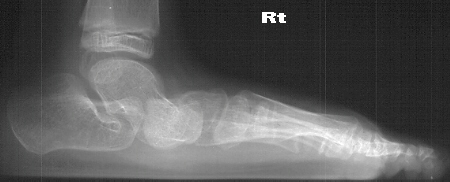

Radiographs reveal the following deformities:

- hindfoot valgus with AP talocalcaneal angle of > 35 degrees

- lateral subluxation/dislocation of the navicular from the talar head

- adduction of the metatarsals with the talus- 1st metatarsal angle to

be divergent medially

- increased lateral talocalcaneal angle with talus plantarflexed on calcaneus

RADIOGRAPHIC FEATURES:

- lateral displacement of the navicular on the head of the talus

- metatarsal adduction

- widening of the talocalcaneal angle on AP radiograph- usually greater

than 35 degrees

- increased lateral talocalcaneal angle with planterflexion of the talus